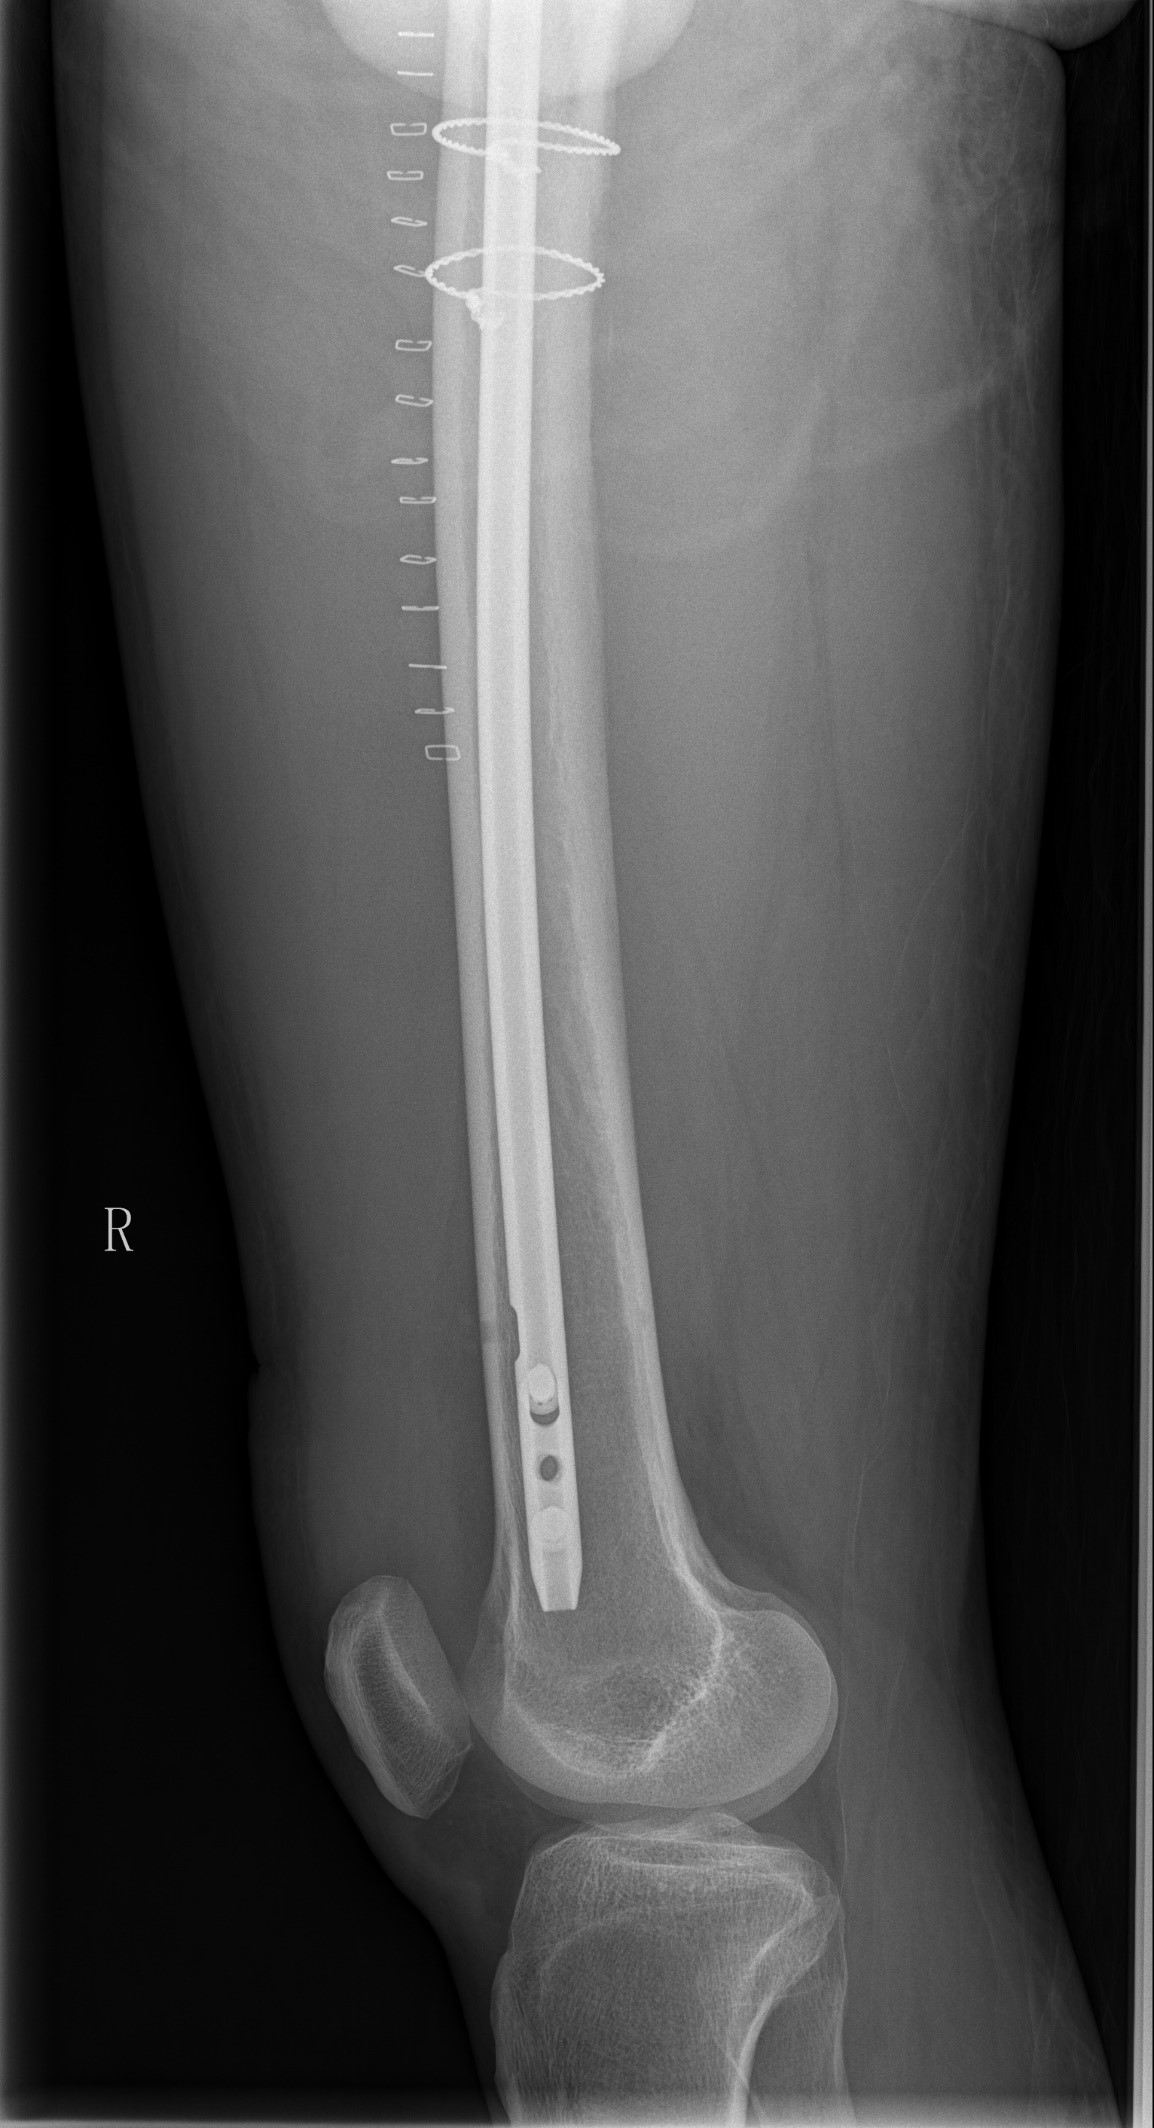

案例一:82岁女性术后再摔伤

患者情况:熊奶奶,一个月前在金瓶梅电影因右髋骨折接受髓内针内固定术,术后康复中因不慎摔倒,再次出现右髋部疼痛并活动受限。经检查,确诊为股骨骨折。患者伴有帕金森病和高血压,身体状况较差。

摔倒原因分析:

术后康复期内,下肢肌力不足;

气温降低,衣物增厚,导致活动灵活性下降。